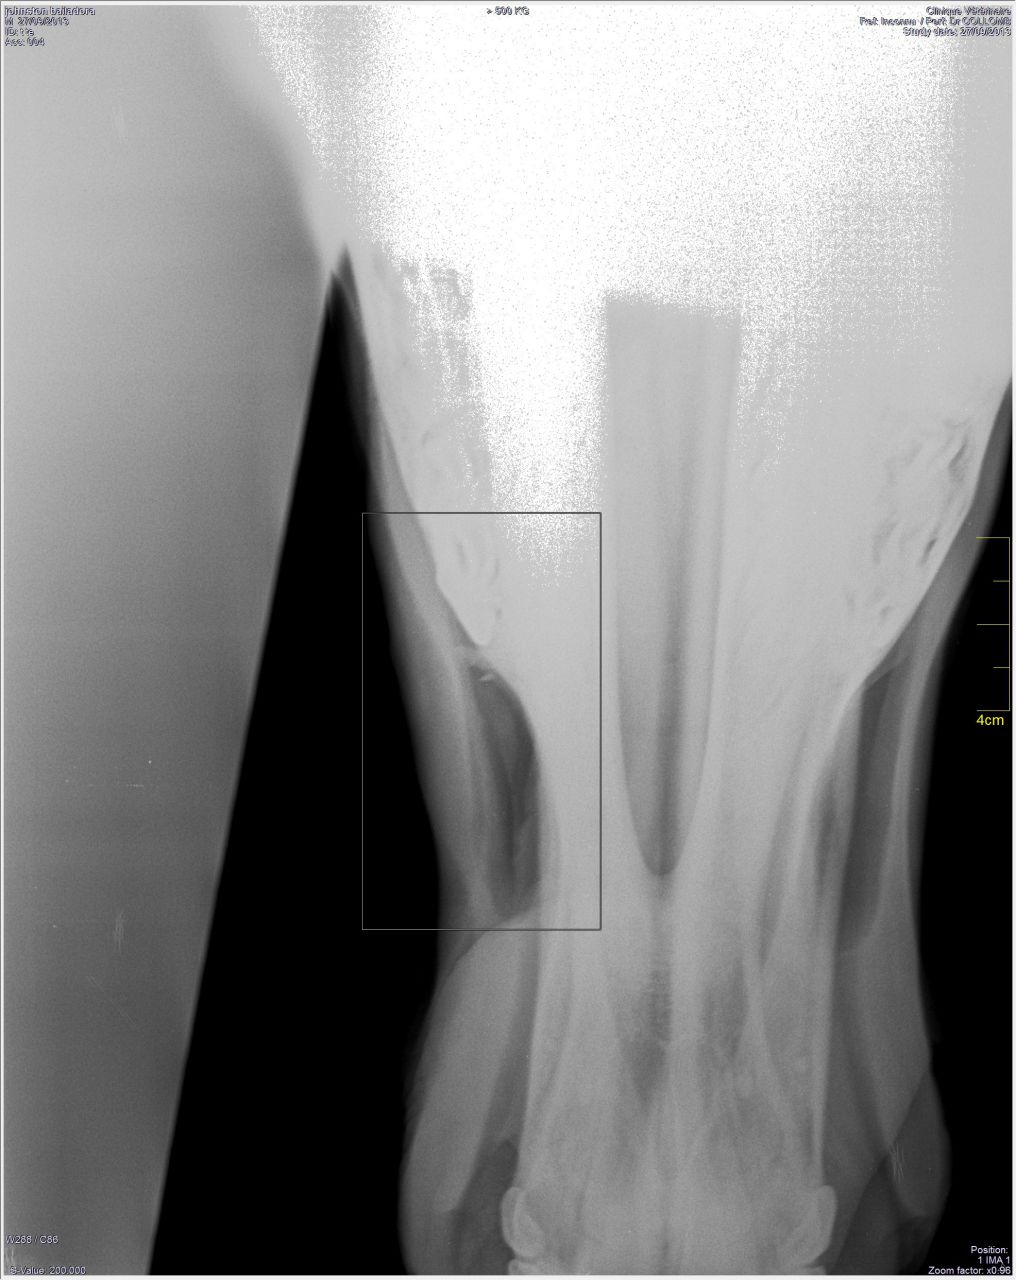

| Dire merci | Et les photos de la bossue! (on voit légèrement la bosse)![]() Et les radios! ![]() ![]() ![]() |